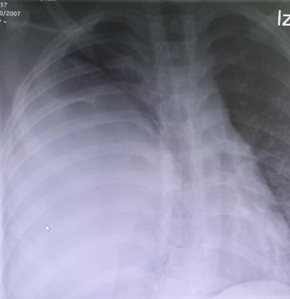

The thoracic scan showed a large tumor measuring 17 x 13 x 11 cm that caused an almost complete collapse of the right main pulmonary artery and deviation of the mediastinum to the contralateral side (Figure 2). The study was completed with a chest MRI, limited by the patient's instability. Comparing it with the previous scan, a greater content of active bleeding was observed at the level of the right lower lobe (Figure 3A, B).

Figure 2 Chest CT Scan: mass measuring 17 x 13 x 11 cm with a significant collapse of the main pulmonary artery and displacement of mediastinal structures.